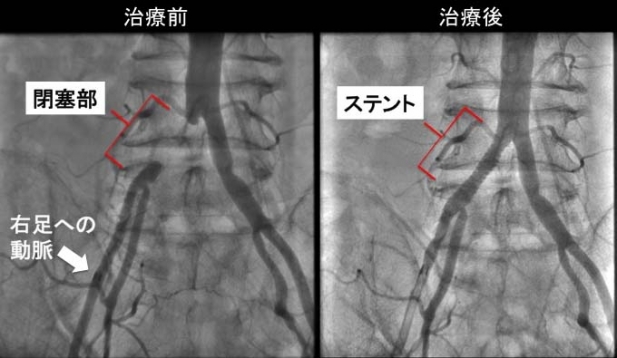

患者さんは4ヶ月前に突然右足の痛み自覚して歩けなくなるという出来事を経験しました。その後も100m歩くと右太ももやふくらはぎの痛みを自覚するとのことでした。このような症状は間歇性跛行(かんけつせいはこう)と呼ばれ、原因としては脊柱管狭窄症という整形外科疾患や動脈硬化による末梢血管疾患(まっしょうけっかんしっかん)が代表的です。足を診察すると右足が冷たく、右足首の脈を触れることができませんでしたので、末梢血管疾患と診断しました。造影CT検査で右足にいく太い血管の付け根が完全に閉塞していることがわかりましたが、細かい血管が末梢とつながっていたため、足が壊死してしまうことはありません。これは道路でいうならば高速は土砂崩れで通行止めですが、一般道により迂回しているといった状態です。幸いなことに閉塞部分の長さは4cm程度でしたので、再開通治療が可能と判断しました。榊原記念病院のカテーテル室をお借りし、右下肢を栄養する血管にステント留置術をさせていただきました(図)。効果は劇的で、その日から症状は完全に消失しました。このような患者さんは動脈硬化の危険因子を改善することが重要です。ヘビースモーカーでしたので当院の禁煙プログラムに参加していただくことにしました。